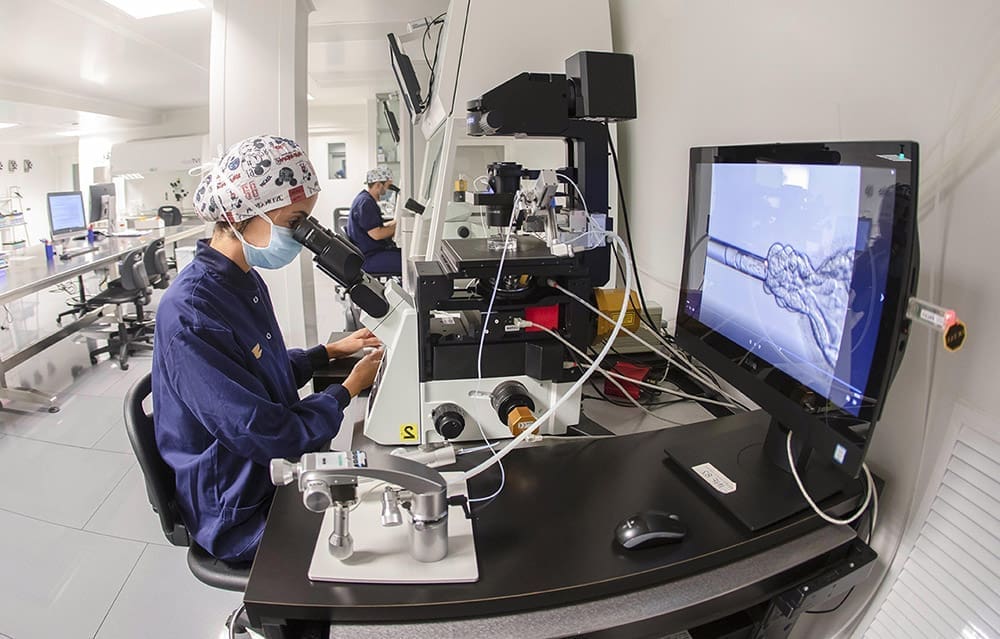

¿Por qué elegir una clínica especializada en alta complejidad reproductiva?

La búsqueda de un embarazo puede llegar a ser un proyecto largo y lleno de incertidumbre, sobre todo cuando el resultado no llega en el momento esperado. Muchas mujeres y […]